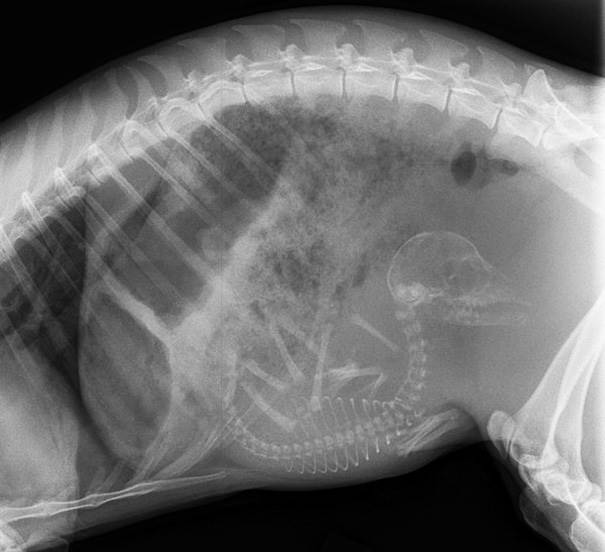

Egy alom kiskutya így néz ki a pocakban. A csúcstartó anyakutya 24 kicsit hordott ki egyszerre. Ezen a képen azért kevesebben vannak, de így sem lehet könnyű.

A kiscicák is elég sokan vannak, és nehéz megkülönböztetni őket a kiskutyáktól így.